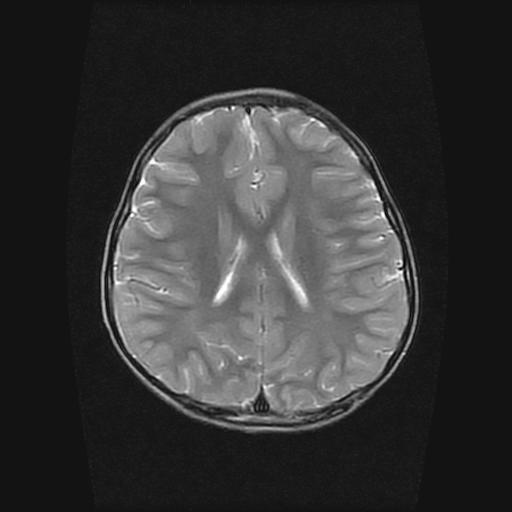

标题: PED0377: 6岁小儿,左侧视神经瘤术后

6岁小儿,左侧视神经瘤术后。现左侧视力减退。